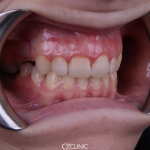

Состояние десневого края

Для эстетической целостности важно, чтобы десневые края были симметричны и находились в правильном положении перед проведением эстетических процедур. Уровни десен можно привести в идеальное положение с помощью лазера или скальпеля